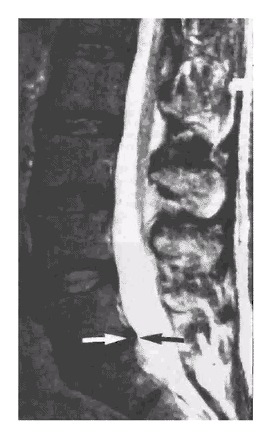

Here are two MRI’s from the study showing a disc protrusion and a disc bulge in two young women with no back pain.

In the discussion section of the study, it states that only 36% of those examined had a normal disc at all levels,

We found a high prevalence of abnormalities in the lumbar spine on MRI examination of people without back pain.

Only 36% of those examined had a normal disc at all levels.

About half had a bulge at at least one intervertebral disc, and about a quarter had at least one disc protrusion.

Given the high prevalence of back pain in the population, the discovery of a bulge or protrusion on an MRI scan in a patient with low back pain may frequently be coincidental.

Therefore, the clinical picture should be correlated with the MRI results.Abnormalities of the lumbar spine by MRI examination can be meaningless if considered in isolation.

Conclusion: An MRI on its own says nothing about your back pain.